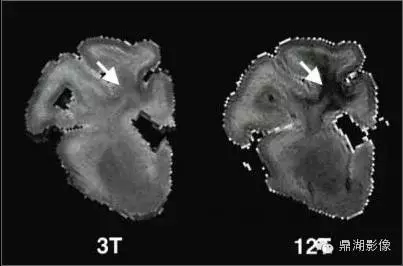

1.磁体系统:磁共振技术发展离不开磁体技术的进步,随着高场强磁体的应用,磁共振技术也进入了功能影像的时代。美国FDA已批准全身3T系统用于临床。4T系统已得到FDA无明显危险的许可。已在7T系统上对几百例健康志愿者完成无事故和无明显安全危险纪录的测试。在9.4T系统上对成年兔及其后代未观察到不良的生物效应。11T、12T系统也早已进入科研。目前磁共振的空间分辨率甚至可以达到0.2毫米的水平,清晰度可以是普通CT的5倍。另外,为了患者检查的舒适度及适应一些特殊类型人群的要求,更大口径的磁体(70cm大孔径磁体)也开始在临床普及。

我们可以清晰的发现12T明显对脑白质损伤更加敏感